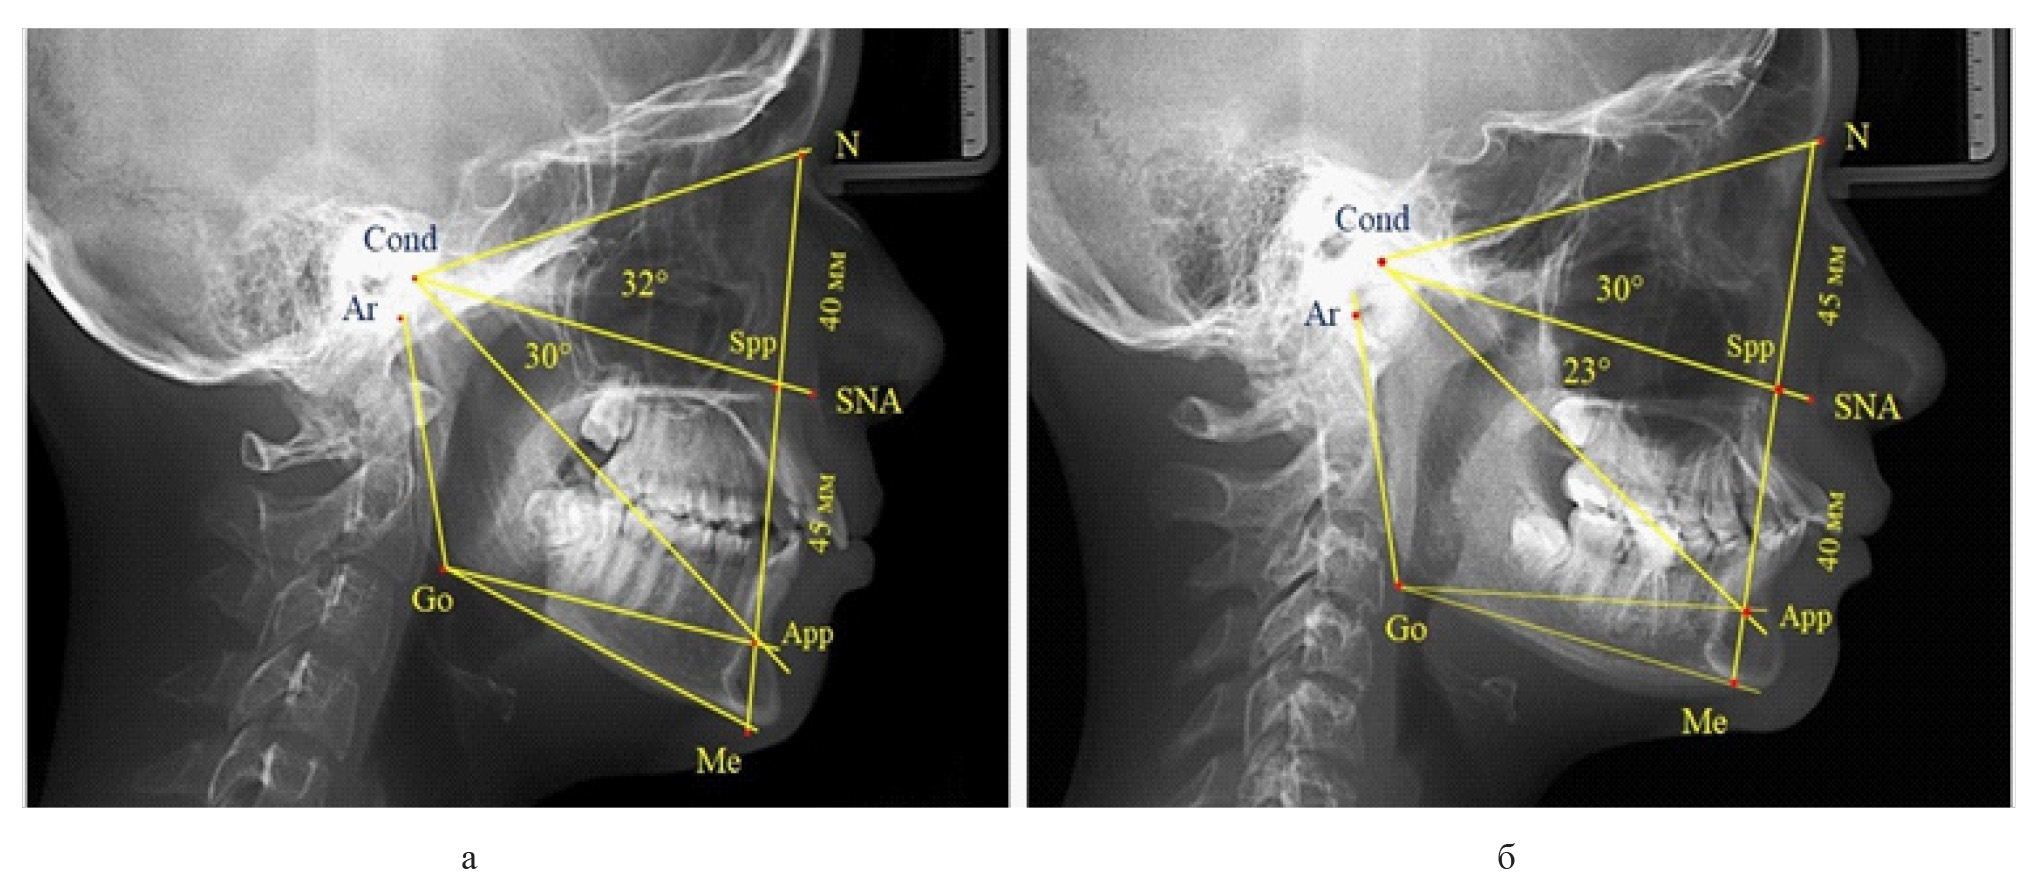

Вертикальная резцовая дизокклюзия (открытый прикус) была проанализирована на 11 телерентгенограммах. При этом отмечались варианты как с оптимальными, так и увеличенными параметрами гнатической части лица при различных типах роста назального отдела, что представлено на рис. 7.

Рис. 7. Сравнительный анализ ТРГ при увеличенных размерах гнатической части с оптимальными (а), укороченными (б) и увеличенными (в) размерами носового отдела лица и вертикальной резцовой дизокклюзией